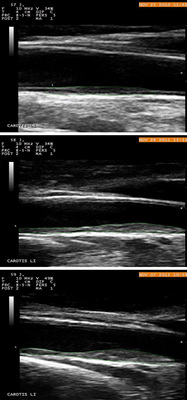

Bisher traten bei 27 Männer und 1 Frau vaskuläre Ereignisse ein (11 Herzinfarkte, 4 Stentimplantationen, 3 Bypass-Operationen, 5 mit Angina pectoris und Koronarstenosen 50 % bis 90 %, 5 er-litten einen Apoplex). Bei 15 Patienten zeigten sich Stenosen < 50 % oder eine Koronarsklerose. Nur 2 Patienten liegen mit ihrer TPA unterhalb des Cut off. Beide erlitten nach 2,5 Jahren einen Herzinfarkt und lagen dann mit ihrer TPA über Cut off.   Abbildung 4 zeigt ein Beispiel für eine Plaqueprogression innerhalb eines Jahres (gleicher Plaque). Die Nachbeobachtungszeit liegt zwischen 1 und 48 Monaten.

Ein weiterer Nachteil ist, dass nur ein kleiner Teil der A. carotis untersucht wird. Die IMT kann bereits bei lateraler oder postero-lateraler Anlotung des gleichen Karotissegments andere Messergebnisse zeigen. Die Messung bis zum hundertstel Millimeter ist nicht unproblematisch und die Dickenzunahme über die Zeitachse ist sehr gering. Bei der TPA-Messung kann innerhalb weniger Monate ein zum Teil erhebliches Plaquewachstum nachgewiesen werden (s. Abb. 4).